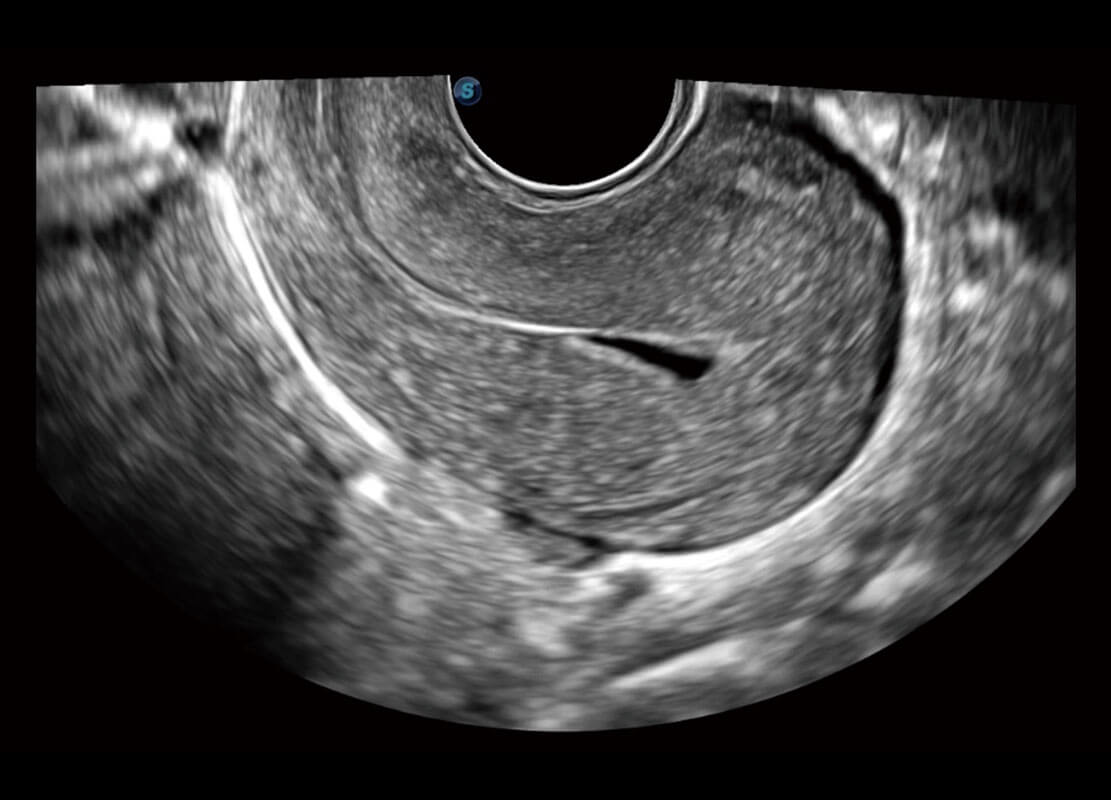

P60優(yōu)異的圖像質(zhì)量搭載專(zhuān)科探頭,在婦科基礎(chǔ)疾病的診斷、卵泡生長(zhǎng)的監(jiān)測(cè)、輸卵管通暢情況的判別等方面為您提供生殖應(yīng)用方案。

腔內(nèi)婦科-宮腔分離

腔內(nèi)婦科-卵巢